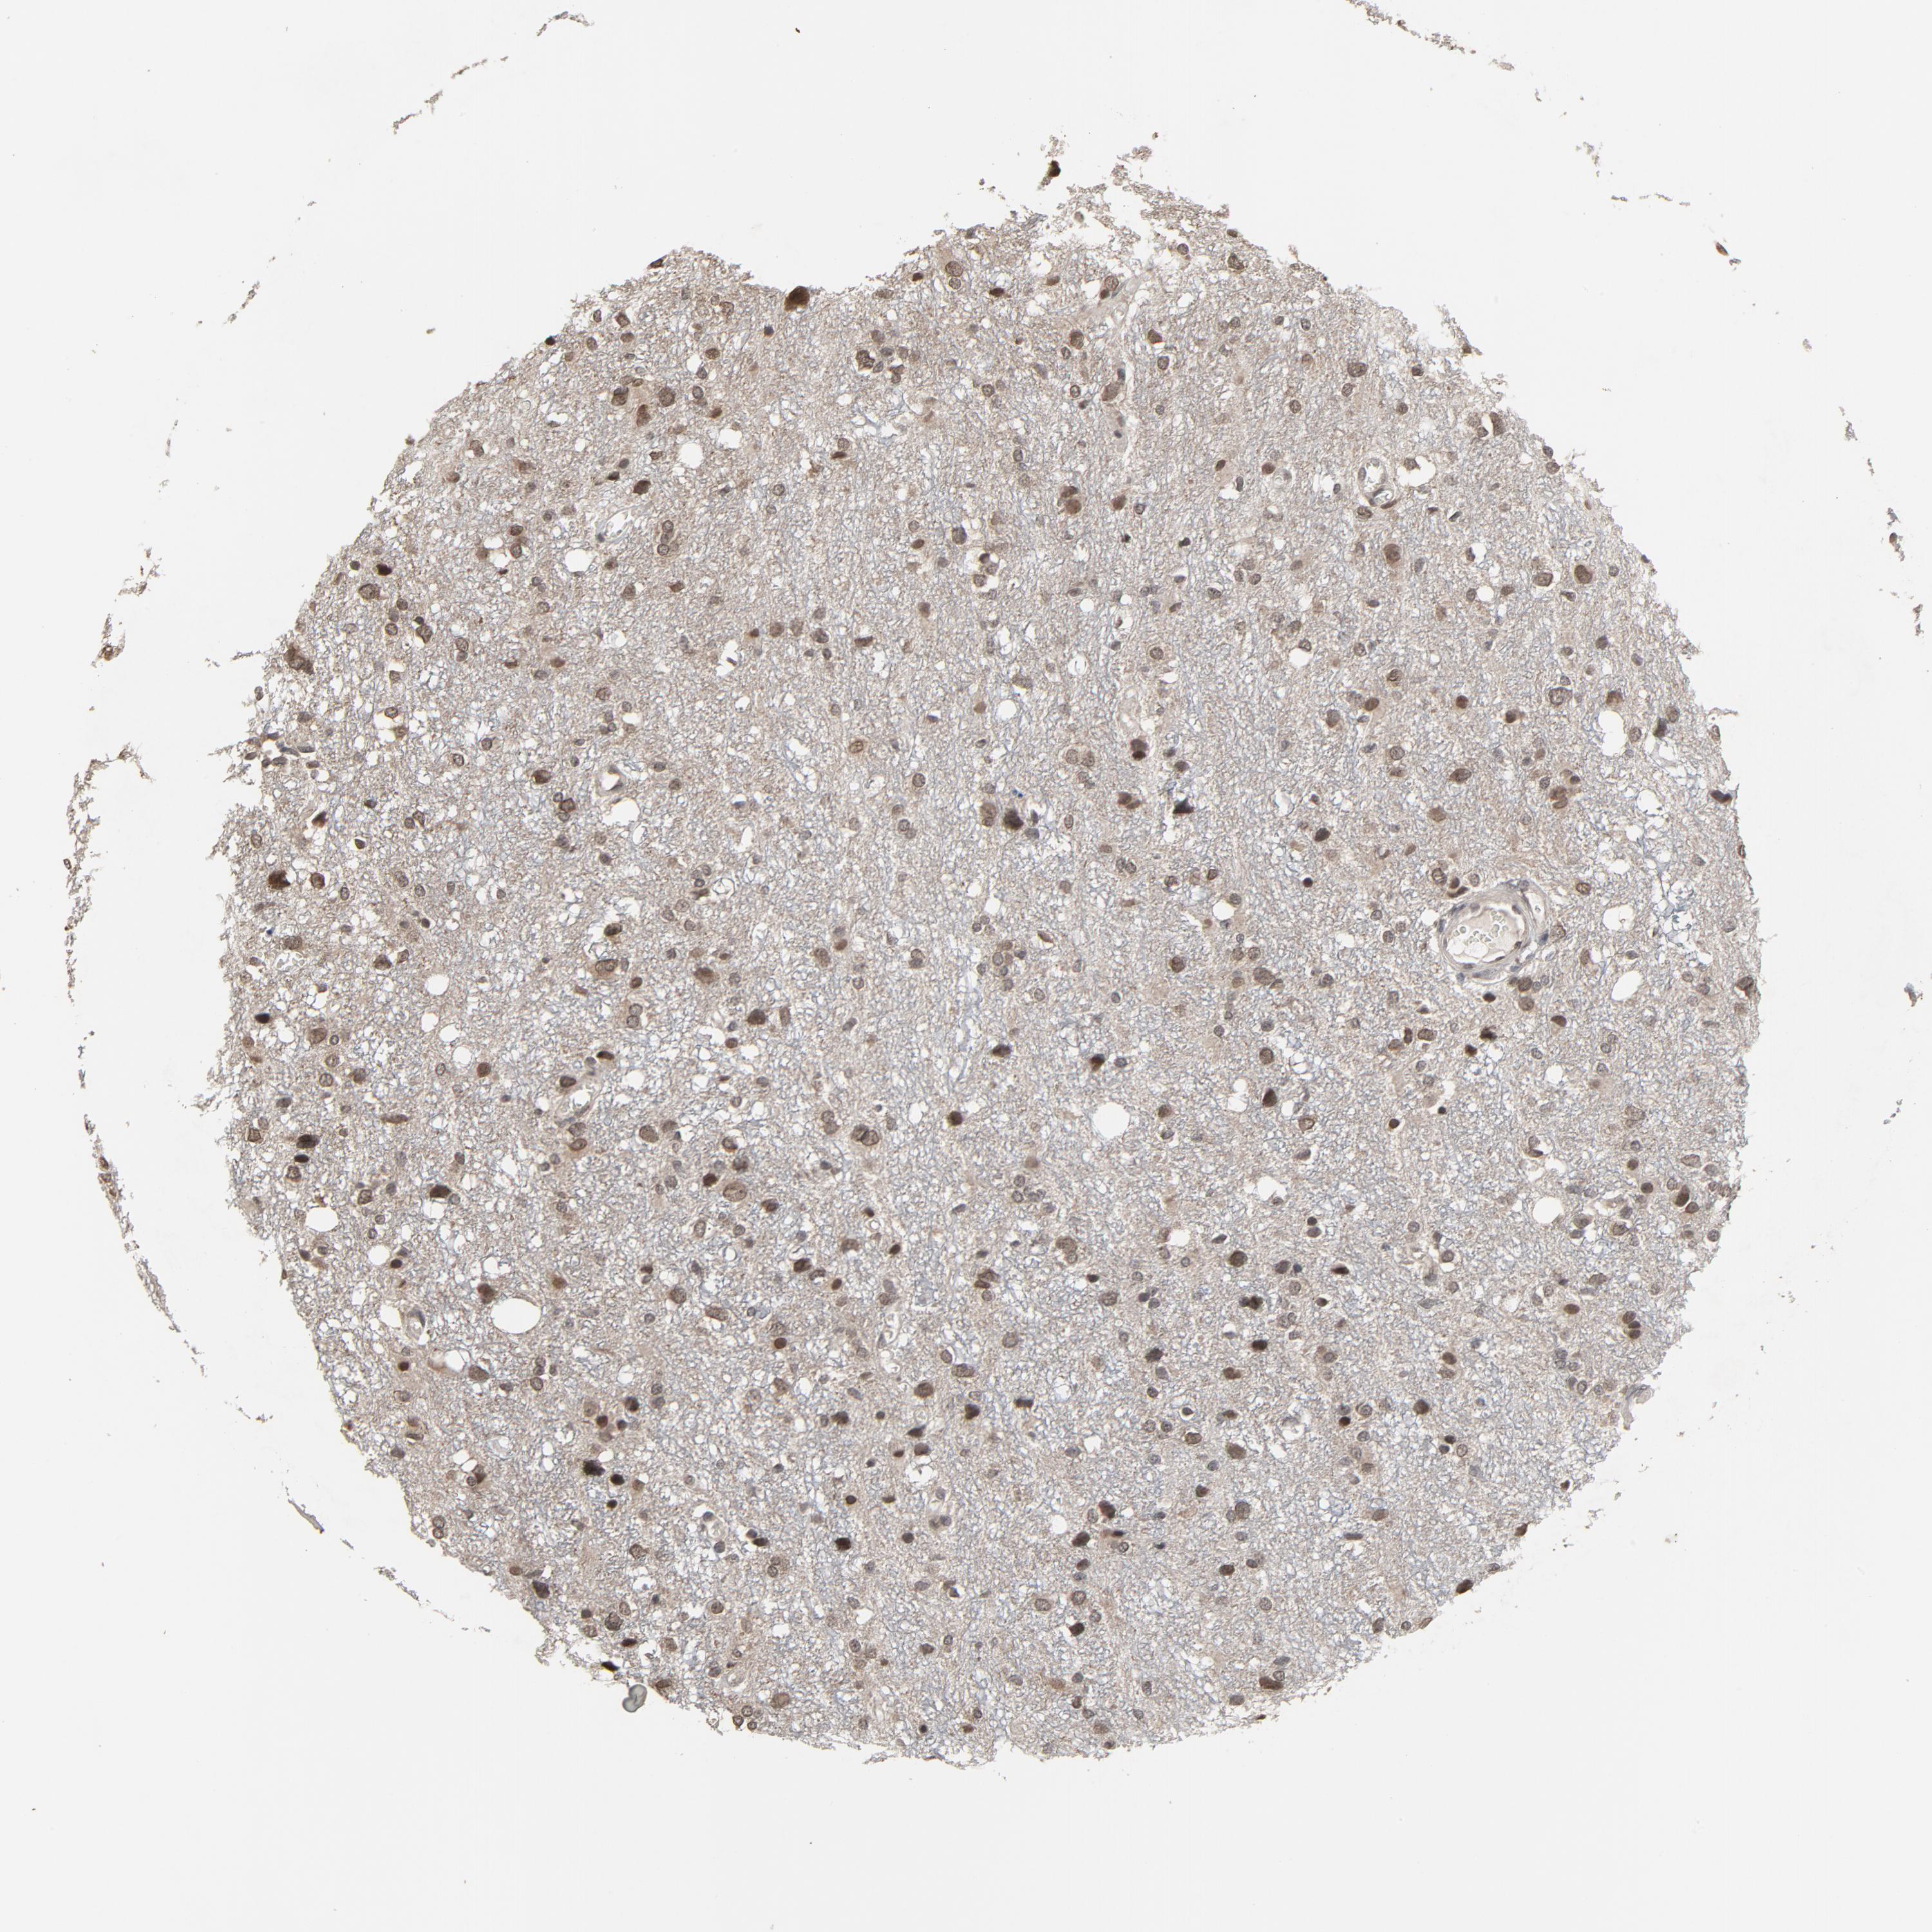

GLIOMA - Protein expressioni

A mouse-over function shows sample information and annotation data. Click on an image to view it in a full screen mode. Samples can be filtered based on level of antibody staining by selecting one or several of the following categories: high, medium, low and not detected. The assay and annotation is described here.

Note that samples used for immunohistochemistry by the Human Protein Atlas do not correspond to samples in the TCGA dataset.

Antibody stainingi

Antibody staining in the annotated cell types in the current human tissue is reported as not detected, low, medium, or high, based on conventional immunohistochemistry profiling in selected tissues. This score is based on the combination of the staining intensity and fraction of stained cells.

Each image is clickable and will lead to virtual microscopy that enables deeper exploration of all samples and also displays staining intensity scores, fraction scores and subcellular localization as well as patient and tissue information for each sample.

Antibody HPA043809

Antibody HPA049817

Antibody CAB003710

Staining

High

Medium

Low

Not detected

Intensity

Strong

Moderate

Weak

Negative

Quantity

>75%

75%-25%

<25%

None

Location

Nuclear

Cytoplasmic/membranous

Cytoplasmic/membranous,nuclear

Glioma, malignant, High grade

Glioma, malignant, Low grade

Glioma, malignant, NOS